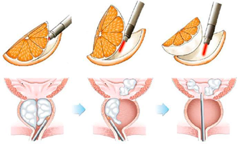

Los STUI derivados del crecimiento benigno de próstata pueden requerir tratamiento médico y en ciertas situaciones pueden requerir tratamiento quirúrgico, el cual clásicamente consiste en cirugía endoscópica a través de la uretra (resección uretral con energía mono o bipolar) sobre todo en próstatas menores a 60 gramos de tamaño y en algunos casos mediante cirugía abierta (Adenomectomía transvesical o retropúbica) en próstatas mayores de 60 gramos o con litiasis vesical (vejiga) asociada, dejando la cirugía laparoscópica o robótica para casos complejos. Sin embargo, el láser para tratamiento del crecimiento benigno de próstata fue descrito por Gilling en 1998 y desde entonces está técnica se ha popularizado y es aplicable en volúmenes de próstata superiores a los que abarcables mediante RTU, demostrando en diversos estudios comparativos con la resección con energía mono o bipolar y la cirugía abierta disminuir el tiempo de necesidad de sonda vesical tras el procedimiento, menor tiempo de hospitalización, menor sangrado. cuestionarios de satisfacción elevados en los pacientes operados con esta técnica y efectos duraderos de la mejoría de síntomas, lo cual hace que actualmente se sitúe como una opción efectiva y duradera para el crecimiento de próstata benigno que requiera cirugía.